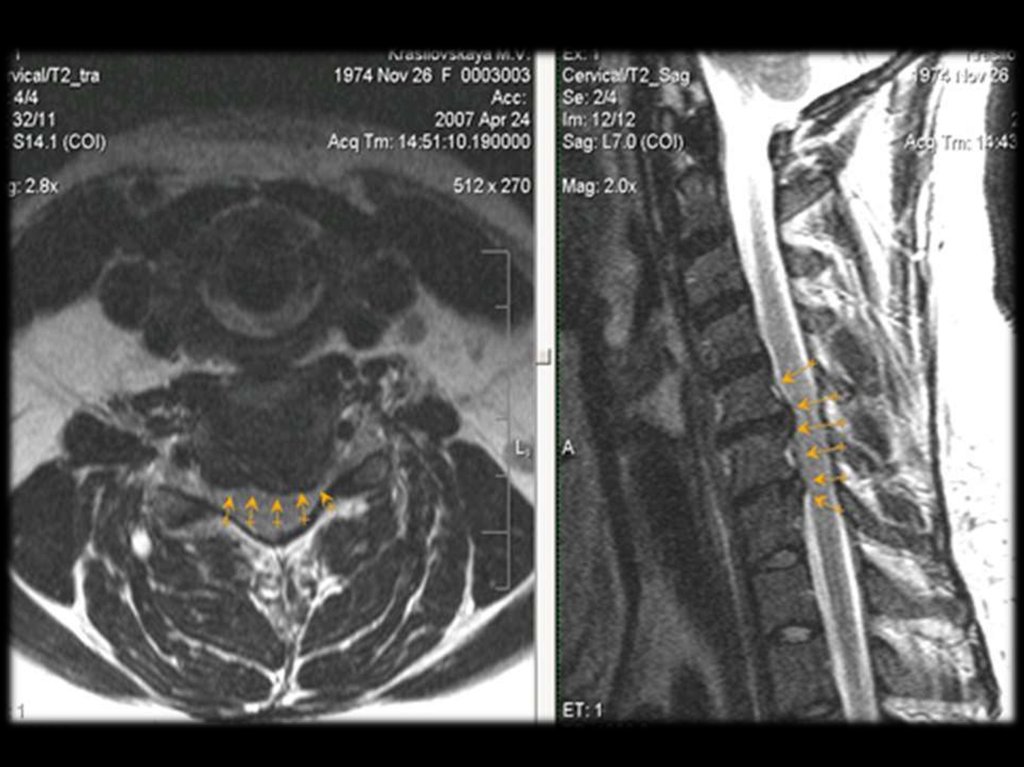

В шейном отделе клинически наиболее значимы

остеофиты

и

артрозы

унковертебральных

сочленений.

остеофиты и артрозы унковертебральных сочленений.

Спинальный стеноз

Сужение просвета спинального канала из-за

выбухания фиброзного кольца в его просвет;

Формирование

остеофитов

в

области

фасеточных суставов;

Врождённый.

Боль возникает при уменьшении диаметра

канала менее 12 мм, при компрессии корешков

“конского хвоста”, при длительной ходьбе.

Характеризуется

следующими

признаками:

двусторонняя,

усиливается

при

нагрузке,

сопровождается парестезиями в голенях. При

выраженном сдавлении развиваются тазовые

расстройства.